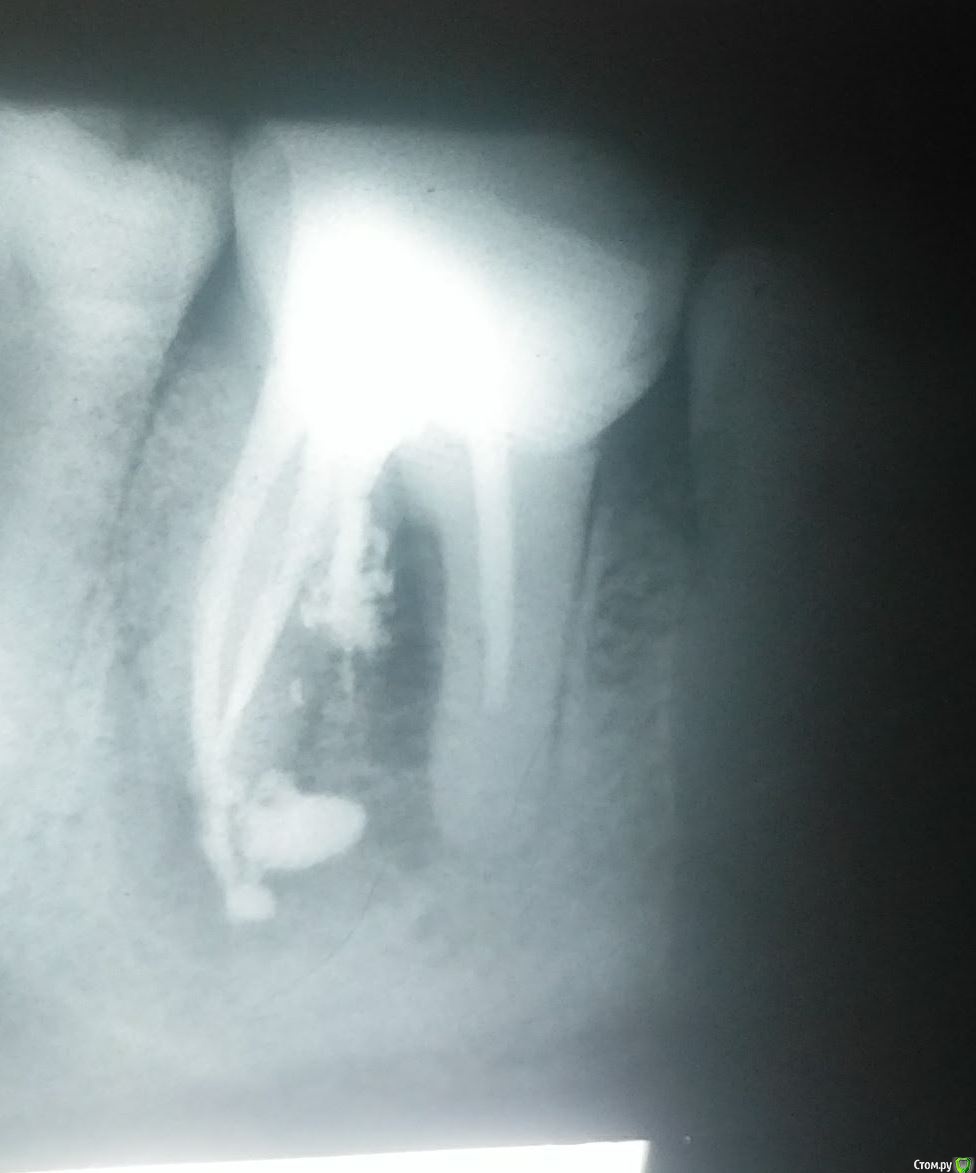

pru2009 Опубликовано 21 февраля, 2018 Поделиться Опубликовано 21 февраля, 2018 Три года тому назад были удалены нервы и установлена пломба на зуб и все было хорошо, но неделю тому назад стало болеть. При обследовании сказали что киста. Стоматолог предложил удаление зуба, но после просьб все-таки заложил лекарство для лечения кисты. Пару дней сильно болело, сейчас боль ушла, опухлость почти прошла, хотя и есть, предлагает на следующей неделе достать лекарство и запломбировать - потом под наблюдение для лечения. Сегодня делал рентген и консультировался с другим стоматологом, он категорически рекомендует удалять зуб и ставить имплант. Посмотрите снимки (это сегодня, лекарство все еще внутри зуба), какое ваше мнение стоит удалять или все-таки можно лечить? Просто жалко зуб удалять если можно вылечить. Ссылка на комментарий

pru2009 Опубликовано 23 февраля, 2018 Автор Поделиться Опубликовано 23 февраля, 2018 если перфорацию надежно закрыть, то еще постоит. Не будьте столь кровожадны )) Меня второй стоматолог напугал тем что на снимке видно что лекарство вытекло в десну, и это якобы ведет к повреждению кости, он меня вообще чуть ли не срочно отправлял на удаление зуба, только стоматолог-хирург к которому направили не взял телефон (видимо готовился к праздникам) поэтому я все еще с зубом.Но сейчас прочитал про перформацию - а получится ли ее закрыть, это ведь получится нужно сейчас убрать лекарство которое вытекло и закрыть канал так чтобы пломбирующий материл тоже не вытек, это без вскрытия десны и операции возможно ли? имею в виду только работая сверху зуба через каналы? или требуется какая-то специфическая операция? Ссылка на комментарий

St. Опубликовано 23 февраля, 2018 Поделиться Опубликовано 23 февраля, 2018 Удалять, закрытие перфорации не решит проблему воспаления между корнями. Если оставить ничего не делая может разболеться в любой неподходящий момент и тогда придется удалять по скорой 1 Ссылка на комментарий

Bier Опубликовано 26 февраля, 2018 Поделиться Опубликовано 26 февраля, 2018 лекарство жить не мешает, оно и рассосаться может постепенно.Если перфорацию надежно закрыть (если это возможно конечно) то и проблема "между корнями" заживет. Ссылка на комментарий